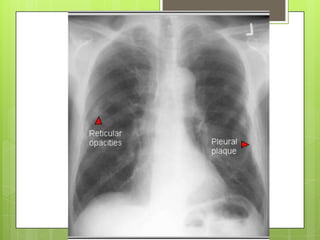

RADIOGRAFÍA Y ESPIROMETRÍA

 Imágenes lineales en campos inferiores y

engrosamiento de pleura parietal 

calcifican (>20 años)

RADIOGRAFÍA Y ESPIROMETRÍA Imágenes lineales en campos inferiores y engrosamiento de pleura parietal  calcifican (>20 años)  Altera precozmente la espirometría: patrón restrictivo REALCION VEF1 /CVF normal o aumentada